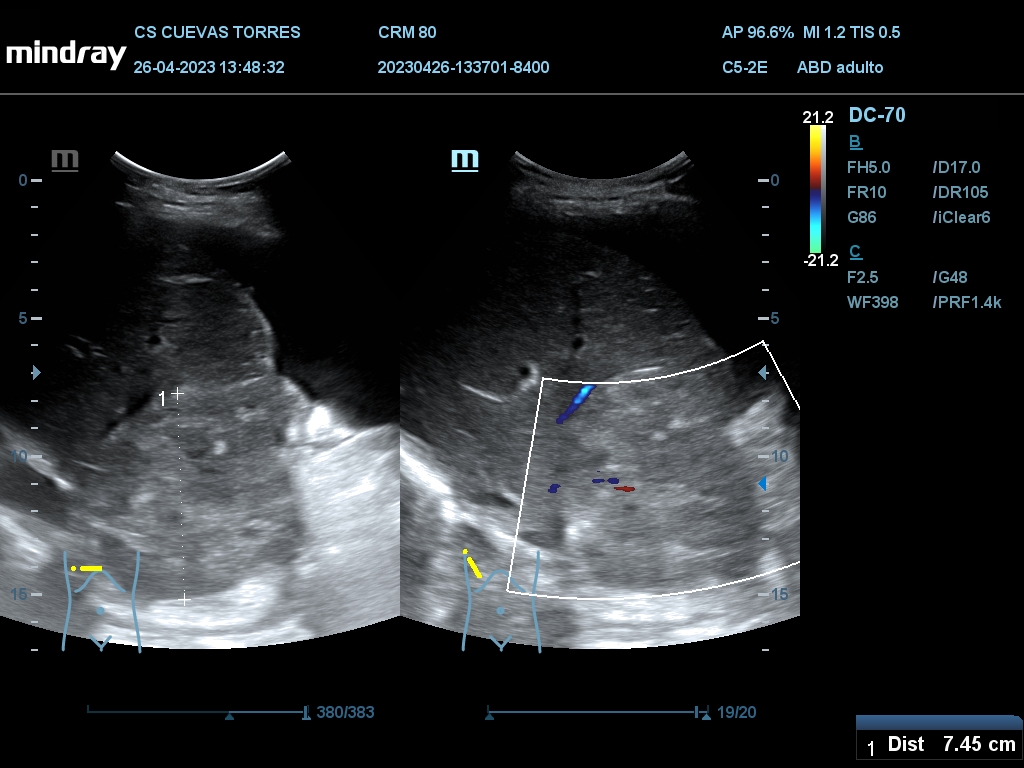

En la ecografía clínica observamos claramente la presencia de líquido libre desde el comienzo de la exploración. Continuando con el estudio Visualizamos circulación portal turbulenta y en el rastreo hepático una lesión ocupante de espacio (LOE) con captación Doppler de 7,45 cm de diámetro máximo.

LOE hepática a estudio.

La paciente fue finalmente diagnosticada de Cáncer de hígado.